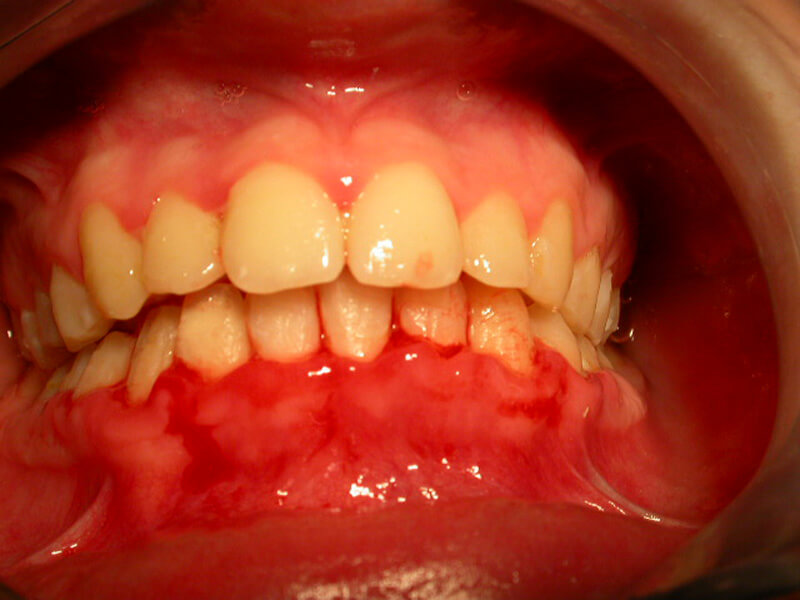

Gingivitis

Gingivitis is caused to the bacterial dental plaque. The main problems related to gingivitis are bleeding from the gums (during tooth brushing), halitosis and swelling of the gums.

Except for the bad oral hygiene, gingivitis is related to hormonal changes during puberty or pregnancy, or the presence of orthodontic mechanisms in the mouth that make difficult to maintain good oral hygiene.